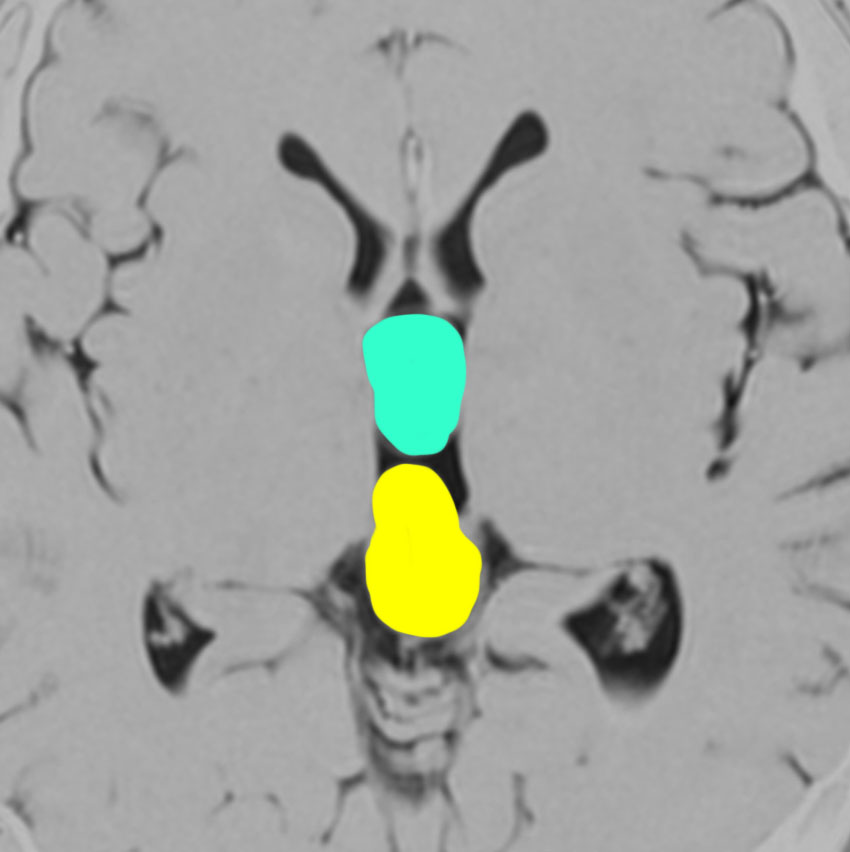

20代の女性に偶然見つかったものです。水色に塗ったのが鞍上部クモ膜のう胞 arachnoid cyst,黄色に塗ったのが松果体のう胞 pineal cystです。両方ともとても珍しもので,大きなのう胞です。クモ膜のう胞と松果体のう胞が同じ原因で形成されることを示唆しています。